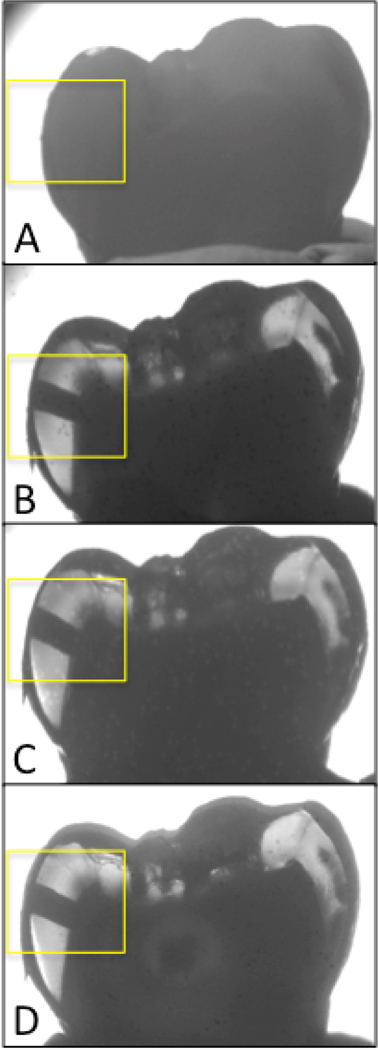

Figure 5 shows NIR occlusal transillumination images and a visible light reflectance image of a tooth with a composite restoration. The contrast is quite low between the composite and surrounding tooth structure for both the reflectance and transillumination visible light image. The composite can be seen with higher contrast in the transillumination image taken at 1300-nm, the composite restoration appears lighter. The contrast is much higher at 1460-nm where the composite is much lighter than the surrounding enamel.

Fig. 5.

Images of a tooth with a composite restoration (Z-250, 3M) in the area of the white box. Transillumination images are shown in for (A) 1460-nm, (B)1300-nm, and (C) visible wavelengths while a visible light reflectance image is shown in D.

A thorough statistical analysis of the measurements on all of the samples will be submitted for publication in a future paper. In summary, it appears that slightly longer NIR wavelengths are likely to have better performance for the transillumination of occlusal caries lesions while 1300-nm appears best for the transillumination of proximal surfaces. Significantly higher performance was attained at wavelengths that have higher water absorption, namely 1460-nm and greater than 1500-nm and these wavelength regions are likely to be more effective for reflectance imaging. Wavelengths with increased water absorption are also likely to be more effective for imaging around composite restorations due to the lower water content of composite as can be seen in Fig. 5.